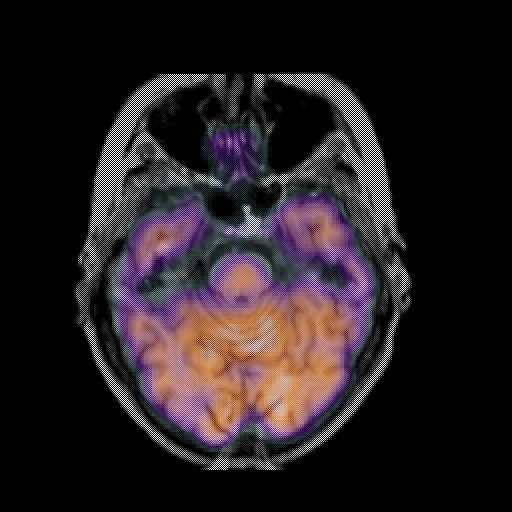

overlay: Slice 17

Slice 17

MRCBFCBF with

T1PDT2T1PDT2